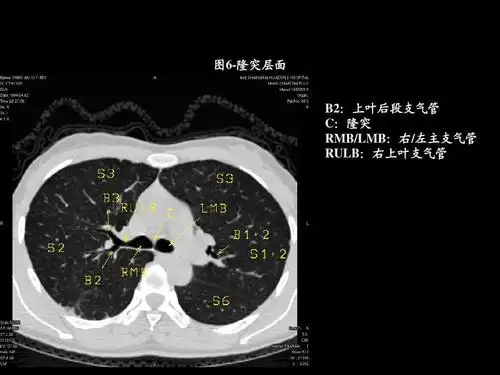

胸部ct的正常结构及肺部疾病的影像学表现ppt